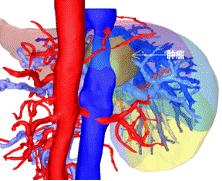

通过CT、磁共振以及三维重建的图像来看,王先生的肿瘤位于肝脏尾状叶,除左侧可见少量肝组织以外,肿瘤已侵犯绝大部分的尾状叶!“跟土豆差不多大!”胡伟表示,王先生的肝脏肿瘤约有5*5*4㎝大小,手术切除对于他来说是目前唯一有效的治疗方案!

3D显示被血管包绕的肿瘤